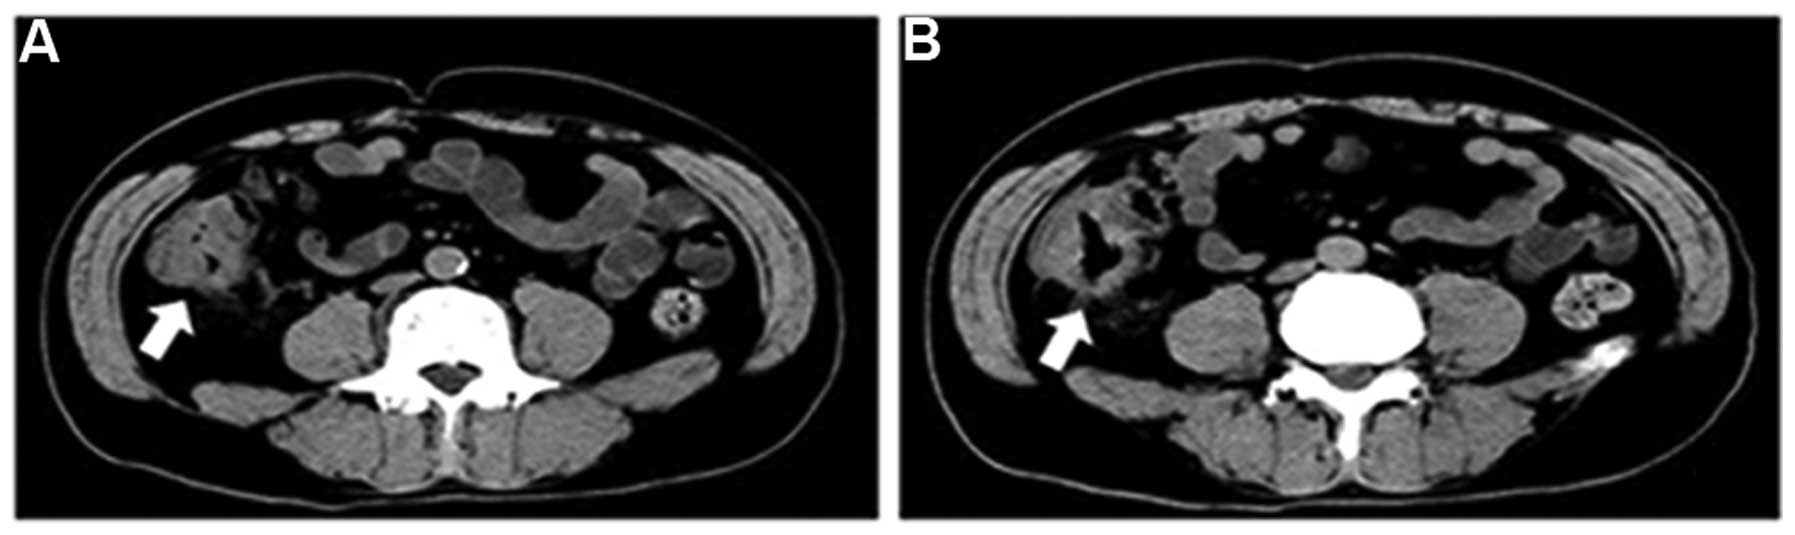

Colorectal Cancer A And B Axial Contrast Enhanced Co Open I

openi.nlm.nih.gov